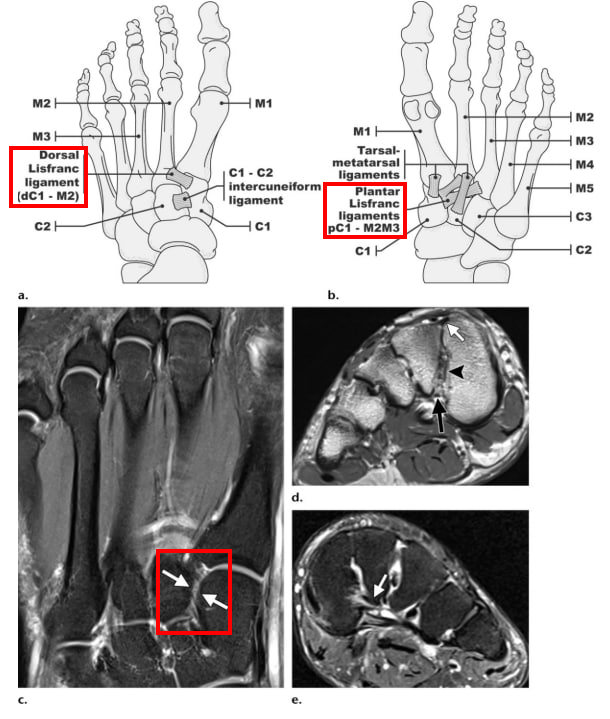

발등면에서, 발가락과 족근골을 연결하여** ## 발을 튼튼하게 받쳐주는 관절**로

발허리뼈(Metatarsal bone) 바닥면과

설상골(Cuneiform bone) 및 입방골(cuboid bone)로 이루어져 있으며,

인대가 뼈를 촘촘하게 감싸서발의 형태를 유지합니다.

5개의 발허리뼈는 횡중족인대에 의해 연결되어 있고,

외측 4개의 발허리뼈 바닥은 서로간에 인대로 연결되어 있는데요.

제1,2 발허리뼈 사이에는 횡중족인대가 없기 때문에 손상에 약한 부위**입니다.

제2 발허리뼈와 설상골을 연결하는 인대를

[리스프랑 인대, Lisfranc ligament]**라고 하여,

이 인대의 손상유무에 따라 관절의 불안정성이 생기기 때문에 매우 중요한 구조물이 됩니다.** > 리스프랑 관절손상, 리스프랑 인대파열 (Lisfranc Ligament)

@ Evaluation of the Tarsometatarsal

Joint Using Conventional Radiography, CT, and MR Imaging. Nasir A Siddiqui, et al. Radiographics

. 2014 Mar-Apr;34(2):514-31.